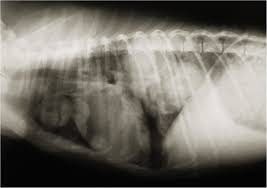

Dogs with high grade (poorly differentiated) tumors with lymph node involvement have an average survival of three months, even with surgery. When the tumors have grown in size and made their way into the lymph nodes of your dog's lymphatic system, the prognosis is far lower, with the average survival time coming in at about two months. It hurts, and feels hopeless, but it's important to remember that it's not necessarily the end of the journey. Pulmonary tumors description — primary lung cancer may arise from any part of the lung but neoplasm of the conducting airways or alveolar parenchyma (functional part of the lungs consisting of the alveoli) are the most common.it accounts for 1% of all neoplasms reported in dogs. During this period you can improve your dog's quality of life by providing extra comfort and affection.

Enjoy This Oncology Article By Sandra M Axiak And Astrid Bigio from d36ai2hkxl16us.cloudfront.net The prognosis is generally good for dogs with primary lung cancer presenting with a single, small mass in their lungs that has not spread to the lymph nodes or other tissue. If a dog has a single primary lung tumor that has not spread to the lymph nodes, he has an average survival time of 12 months. There are various types of carcinoma. A dog with a single primary lung tumor that has not spread to the lymph nodes has the longest average survival time (an average of 12 months); For dogs with small, low grade (well differentiated) tumors without lymph node involvement, the average survival time is 16 months or longer with surgery alone. Most primary lung tumors are a type of cancer called carcinoma. Dogs treated for a single primary lung tumor which has not spread to the lymph nodes have an average survival time of about 12 months, however if the dog's lymph nodes also show signs of cancer, or if multiple tumors are found, life expectancy is only about 2 months. For small, solitary tumors that have not metastasized (spread), the average survival time with surgery alone is 20 months.

If a dog is experiencing any serious respiratory symptoms or decline in their health, this is often a sign that the cancer is severe or it has spread to other parts of the body. For dogs with small, low grade (well differentiated) tumors without lymph node involvement, the average survival time is 16 months or longer with surgery alone. You can spend a lot of money on invasive diagnostic tests like bronchoalveolar lavage … and never really know exactly what the cause is. When the tumors have grown in size and made their way into the lymph nodes of your dog's lymphatic system, the prognosis is far lower, with the average survival time coming in at about two months. Lung cancer in pets is rare. A dog diagnosed and treated for a single primary lung tumor that has not spread to the lymph nodes has an average survival time of about 12 months, however, if the dog's lymph nodes also show signs of cancer or if multiple tumors are found life expectancy is only about 2 months. As the cancer grows, dogs may develop a cough, difficulty breathing, and other symptoms. The second kind of lung cancer in dogs is called metastatic lung cancer, which means the cancer originated somewhere else in the body, but has spread to the lung. Dogs with high grade (poorly differentiated) tumors with lymph node involvement have an average survival of three months, even with surgery. In this group, more than 50% are expected to live 1 year after the surgical removal of the mass. In this group, more than 50% are expected to live 1 year after the surgical removal of the mass. The lung is the most common location for metastatic osteosarcoma. From a medical perspective, having a dog live the average lifespan is a good result.

As best as you can, be attentive to your dog's breathing patterns, and protect it from exposure to second hand smoke. For small, solitary tumors that have not metastasized (spread), the average survival time with surgery alone is 20 months. If a dog is experiencing any serious respiratory symptoms or decline in their health, this is often a sign that the cancer is severe or it has spread to other parts of the body. In general, the prognosis for treating cases of metastatic cancer in dogs depends on how early the metastatic tumor is identified and how invasive it is. Following are some symptoms of end stage lung cancer in dogs and some tips for those who chose to provide their dog with some hospice care. End stage lung cancer in dogs will cause the. In this group, more than 50% are expected to live 1 year after the surgical removal of the mass. Pulmonary adenocarcinoma is cancer of the lungs, which can be primary (originates in the lungs) or secondary (originates somewhere else in the body), is a serious disease that can be fatal if not found and treated early. The lung is the most common location for metastatic osteosarcoma. Recovery of metastic neoplasia (cancer) in dogs unfortunately, the prognosis for metastatic neoplasia is grave due to the fact that the cancer has already spread. In this group, more than 50% are expected to live 1 year after the surgical removal of the mass. If, on the other hand, the dog has multiple tumors, or if the cancer has spread to the lymph nodes, the life expectancy is only about 2 months. Primary lung cancer, which is quite rare and metastatic lung cancer, spread from other areas of the body.

If a dog has a single primary lung tumor that has not spread to the lymph nodes, he has an average survival time of 12 months. If the lymph nodes are involved or multiple tumors are found at the time of diagnosis, survival time is shortened to only 2 months. For dogs with small, low grade (well differentiated) tumors without lymph node involvement, the average survival time is 16 months or longer with surgery alone. Dogs treated for a single primary lung tumor which has not spread to the lymph nodes have an average survival time of about 12 months, however if the dog's lymph nodes also show signs of cancer, or if multiple tumors are found, life expectancy is only about 2 months. The prognosis is good for dogs with primary lung cancer presents with a single, small mass in their lungs that has not spread to lymph nodes or other tissues.